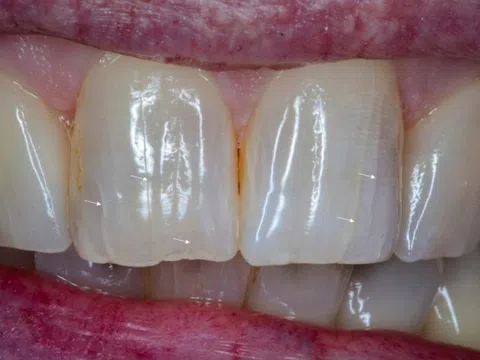

Tưởng vô hại, các vết rạn trên răng có thể gây rắc rối lớn

12:00 24/12/2025

Không gây đau hay ê buốt, những vết rạn trên răng đang xuất hiện ngày càng sớm và có thể kéo theo nhiều vấn...